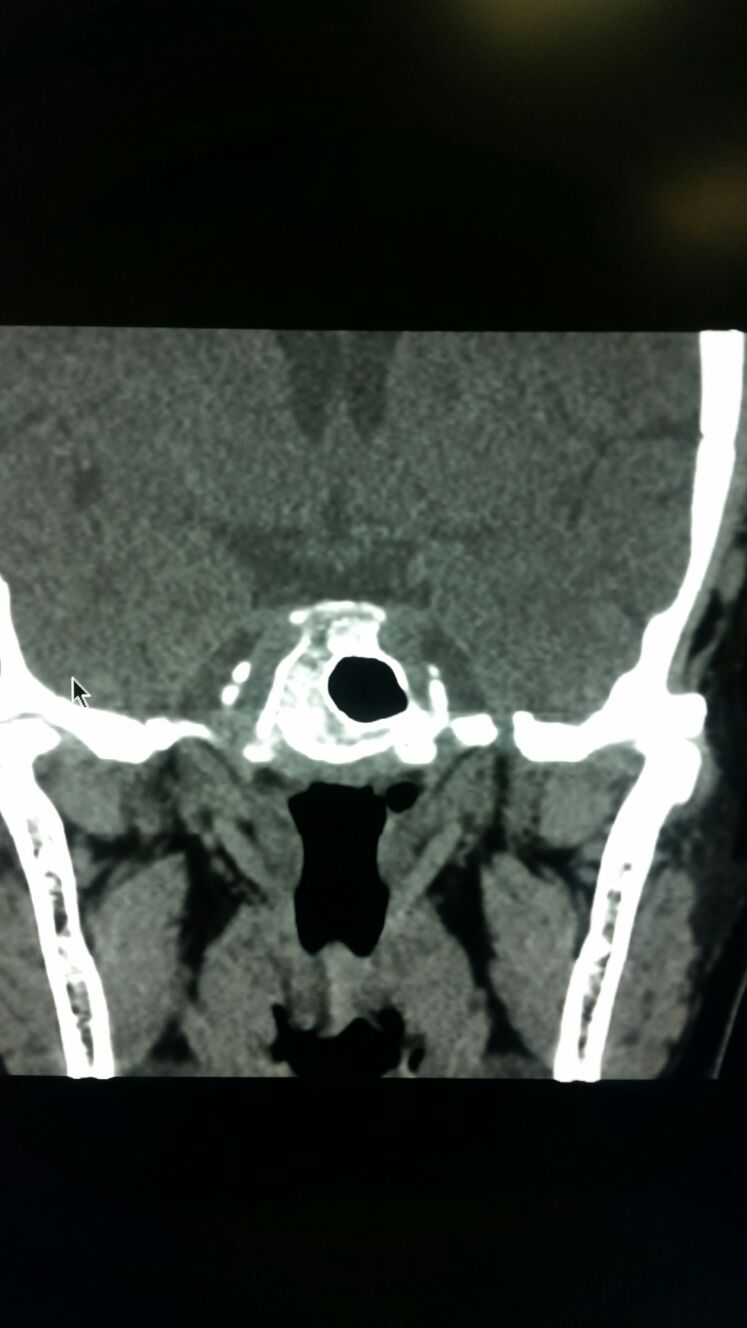

女,32岁,鼻窦炎,感觉鼻腔空虚,常常下午头疼,具体部位(左眉愣骨区)感觉左鼻腔吸气就疼,呼气时候比较舒服,不能受风,有特殊治疗办法吗?